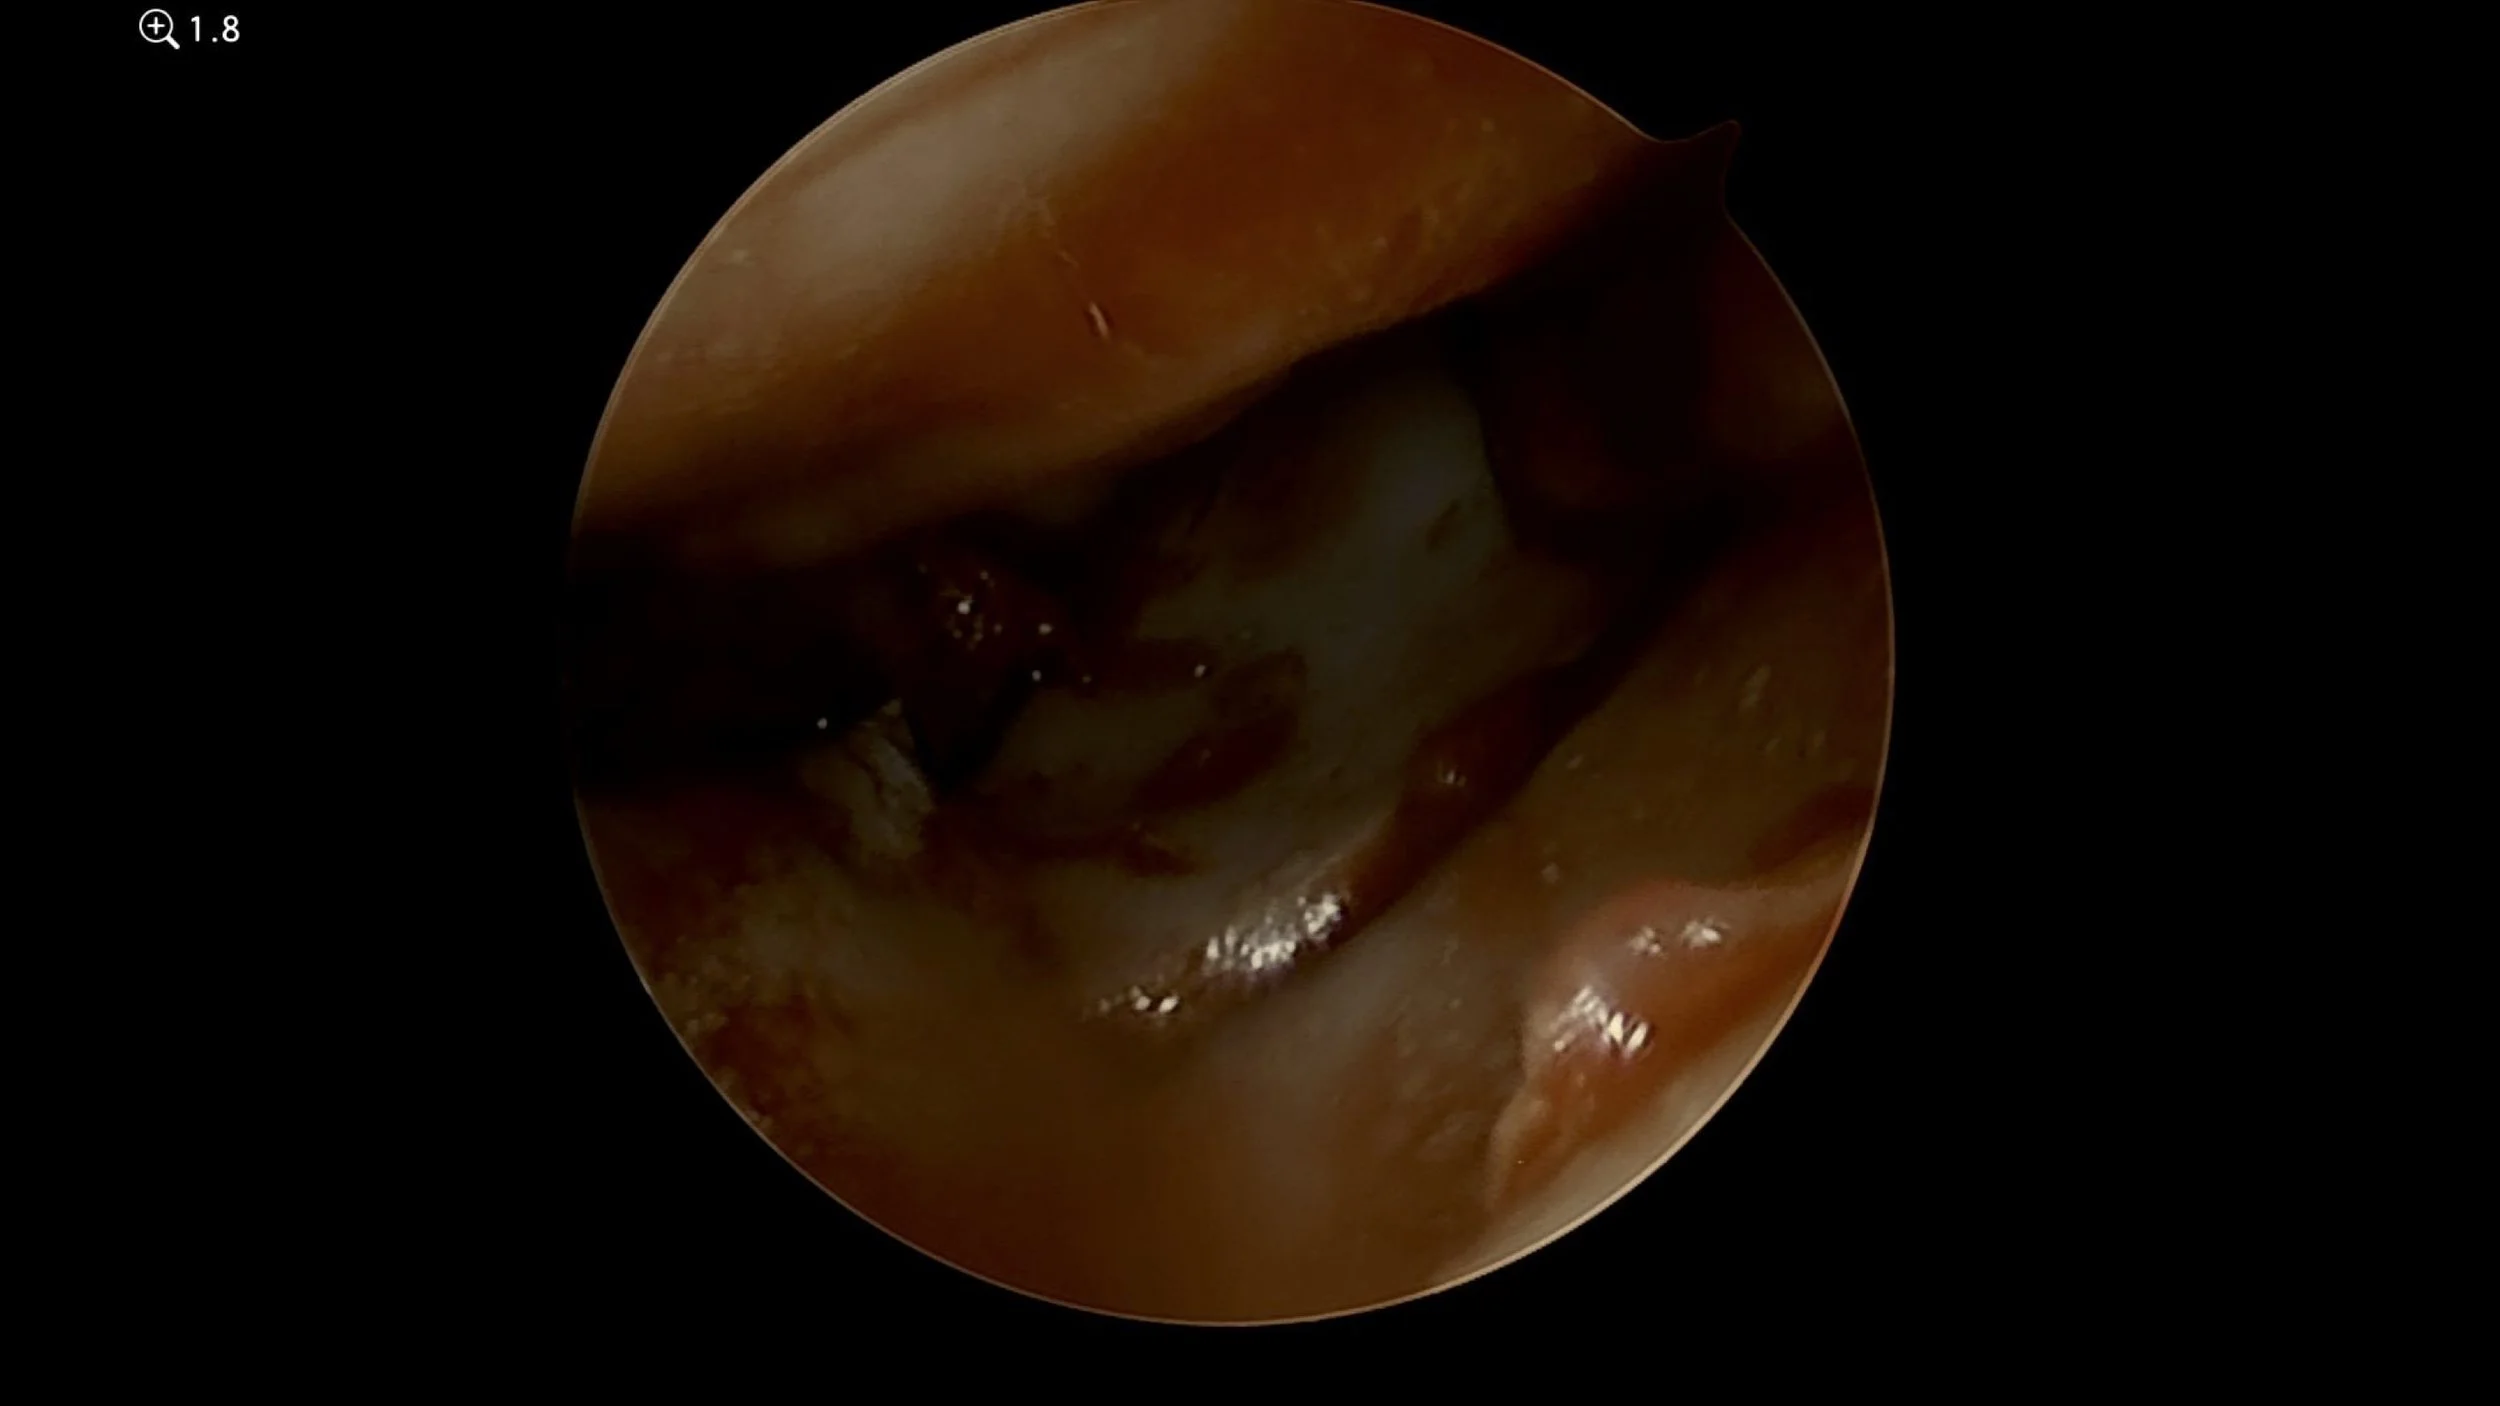

Scaphoid nonunions ( scaphoid fracture that has not healed) can be cleaned out and bone graft inserted arthroscopically before a headless screw is inserted.

Wrist arthroscopy keyhole scaphoid surgery looking at an unhealed nonunion fracture